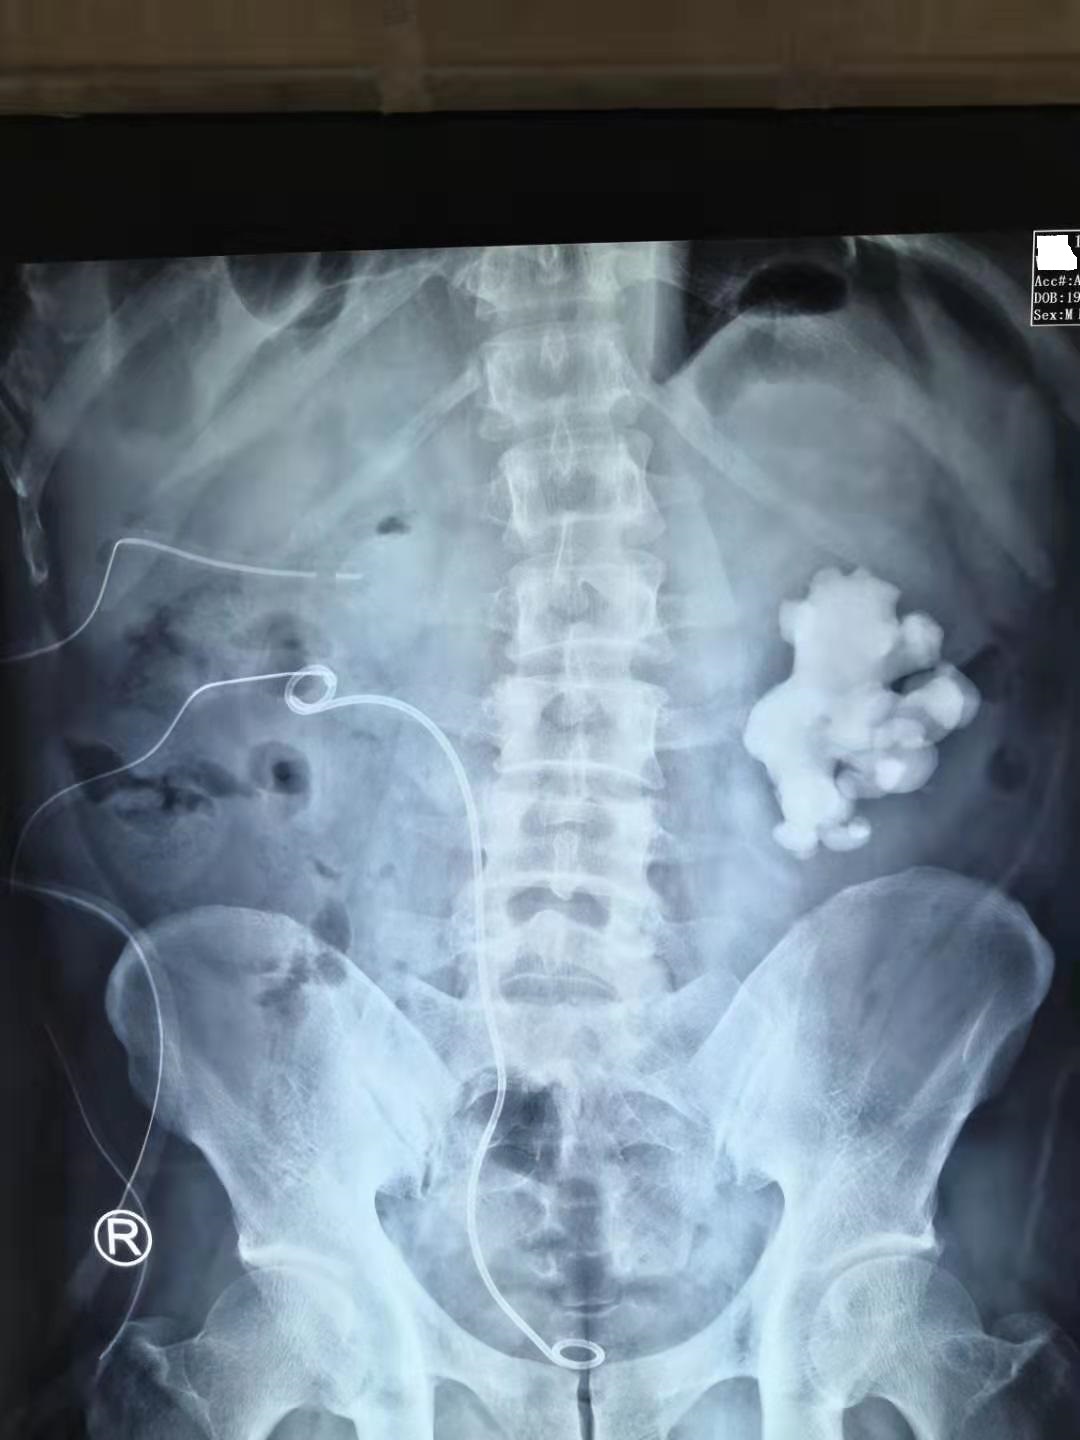

然后第二次手术选择分期处理左肾鹿角形结石,先把左侧肾脏约50%的结石负荷。

第二次手术取出50%左肾结石

最后第三次手术把左侧肾脏剩下的50%结石彻底清除。这三次手术前后历时10天,最终把林先生的双肾鹿角形结石清除干净。

第三次手术取净左肾结石!